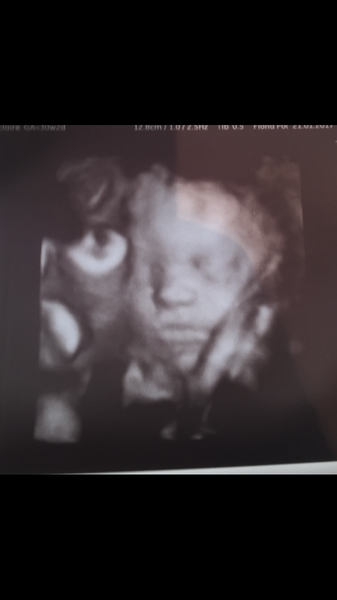

On the gap between scans- I have absolutely considered booking a couple of private ones in. I have zero financial grounds to do this, but I don't care!!! I've impulse bought shoes with less consideration. My 20 week midwife appointment is going to actually be at 24 weeks (30th Jan) thanks to work commitments and a waiting list so a bit of extra reassurance would be great right now.

Thought about trying to get one this week as my already low bump appears to have got even lower today? I had low backache this morning too, which sent me into a panic, naturally. I have a low lying placenta but didn't think the two were related?